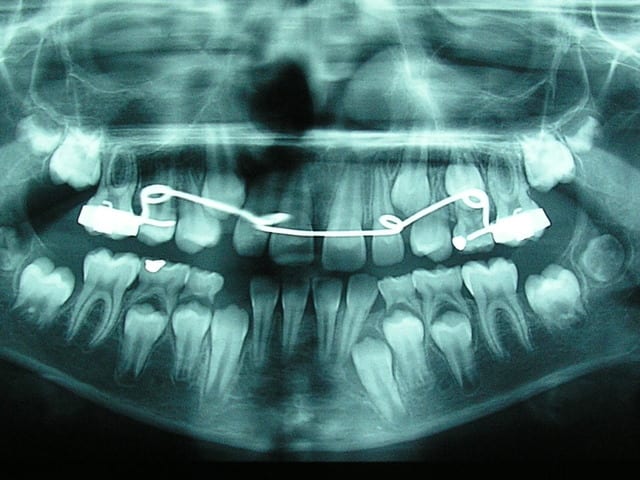

pour faire suite à la question de bjc les incisives maxillaire ont une taille normale de 9 mm, voici la pano et une photo du maxillaire aujourd'hui.

Quel pronostic pour la cabine mandibulaire gauche?